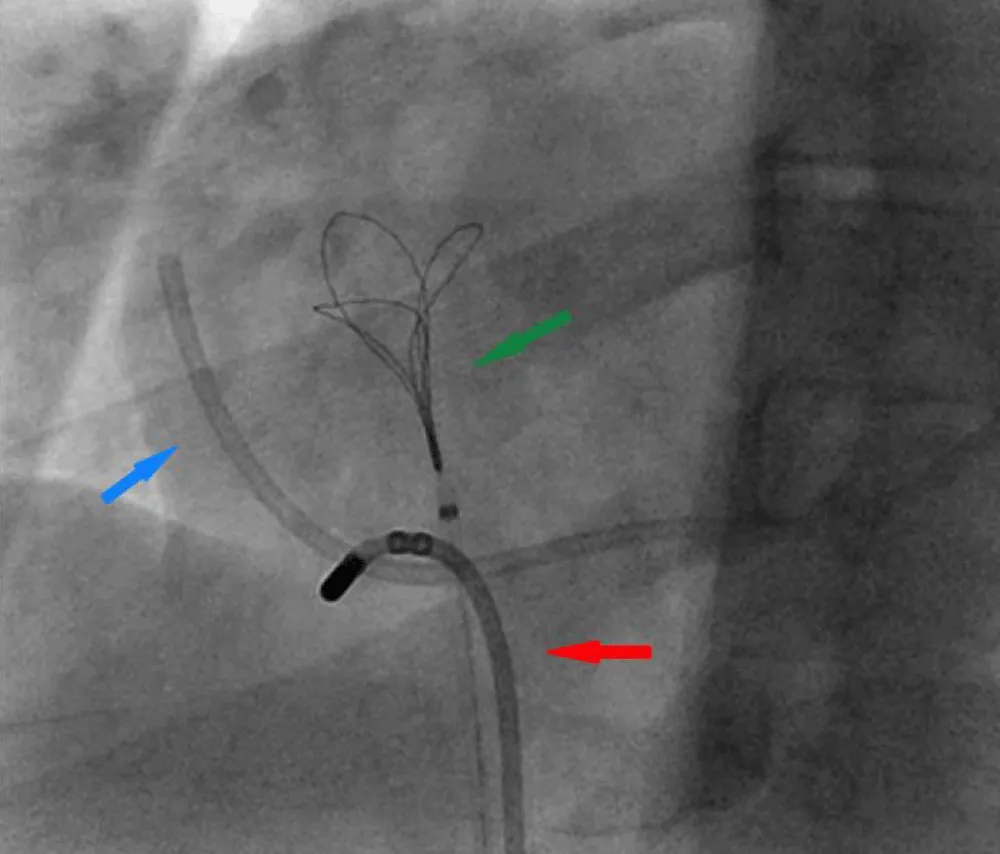

Therefore, further retrieval attempts using multiple catheters to hook the port over the tricuspid valve were unsuccessful. Finally, a navigational electrophysiology steerable catheter was used to hook the port over the tricuspid valve (Figure 3 and Video 1 Click here.

Figure 3: Right Heart catheterization shows a Navigational steerable catheter hooking the port and disengaging it from the coronary sinus. Fractured Port (blue arrow), Navigational steerable catheter (red arrow), Snare (green arrow).